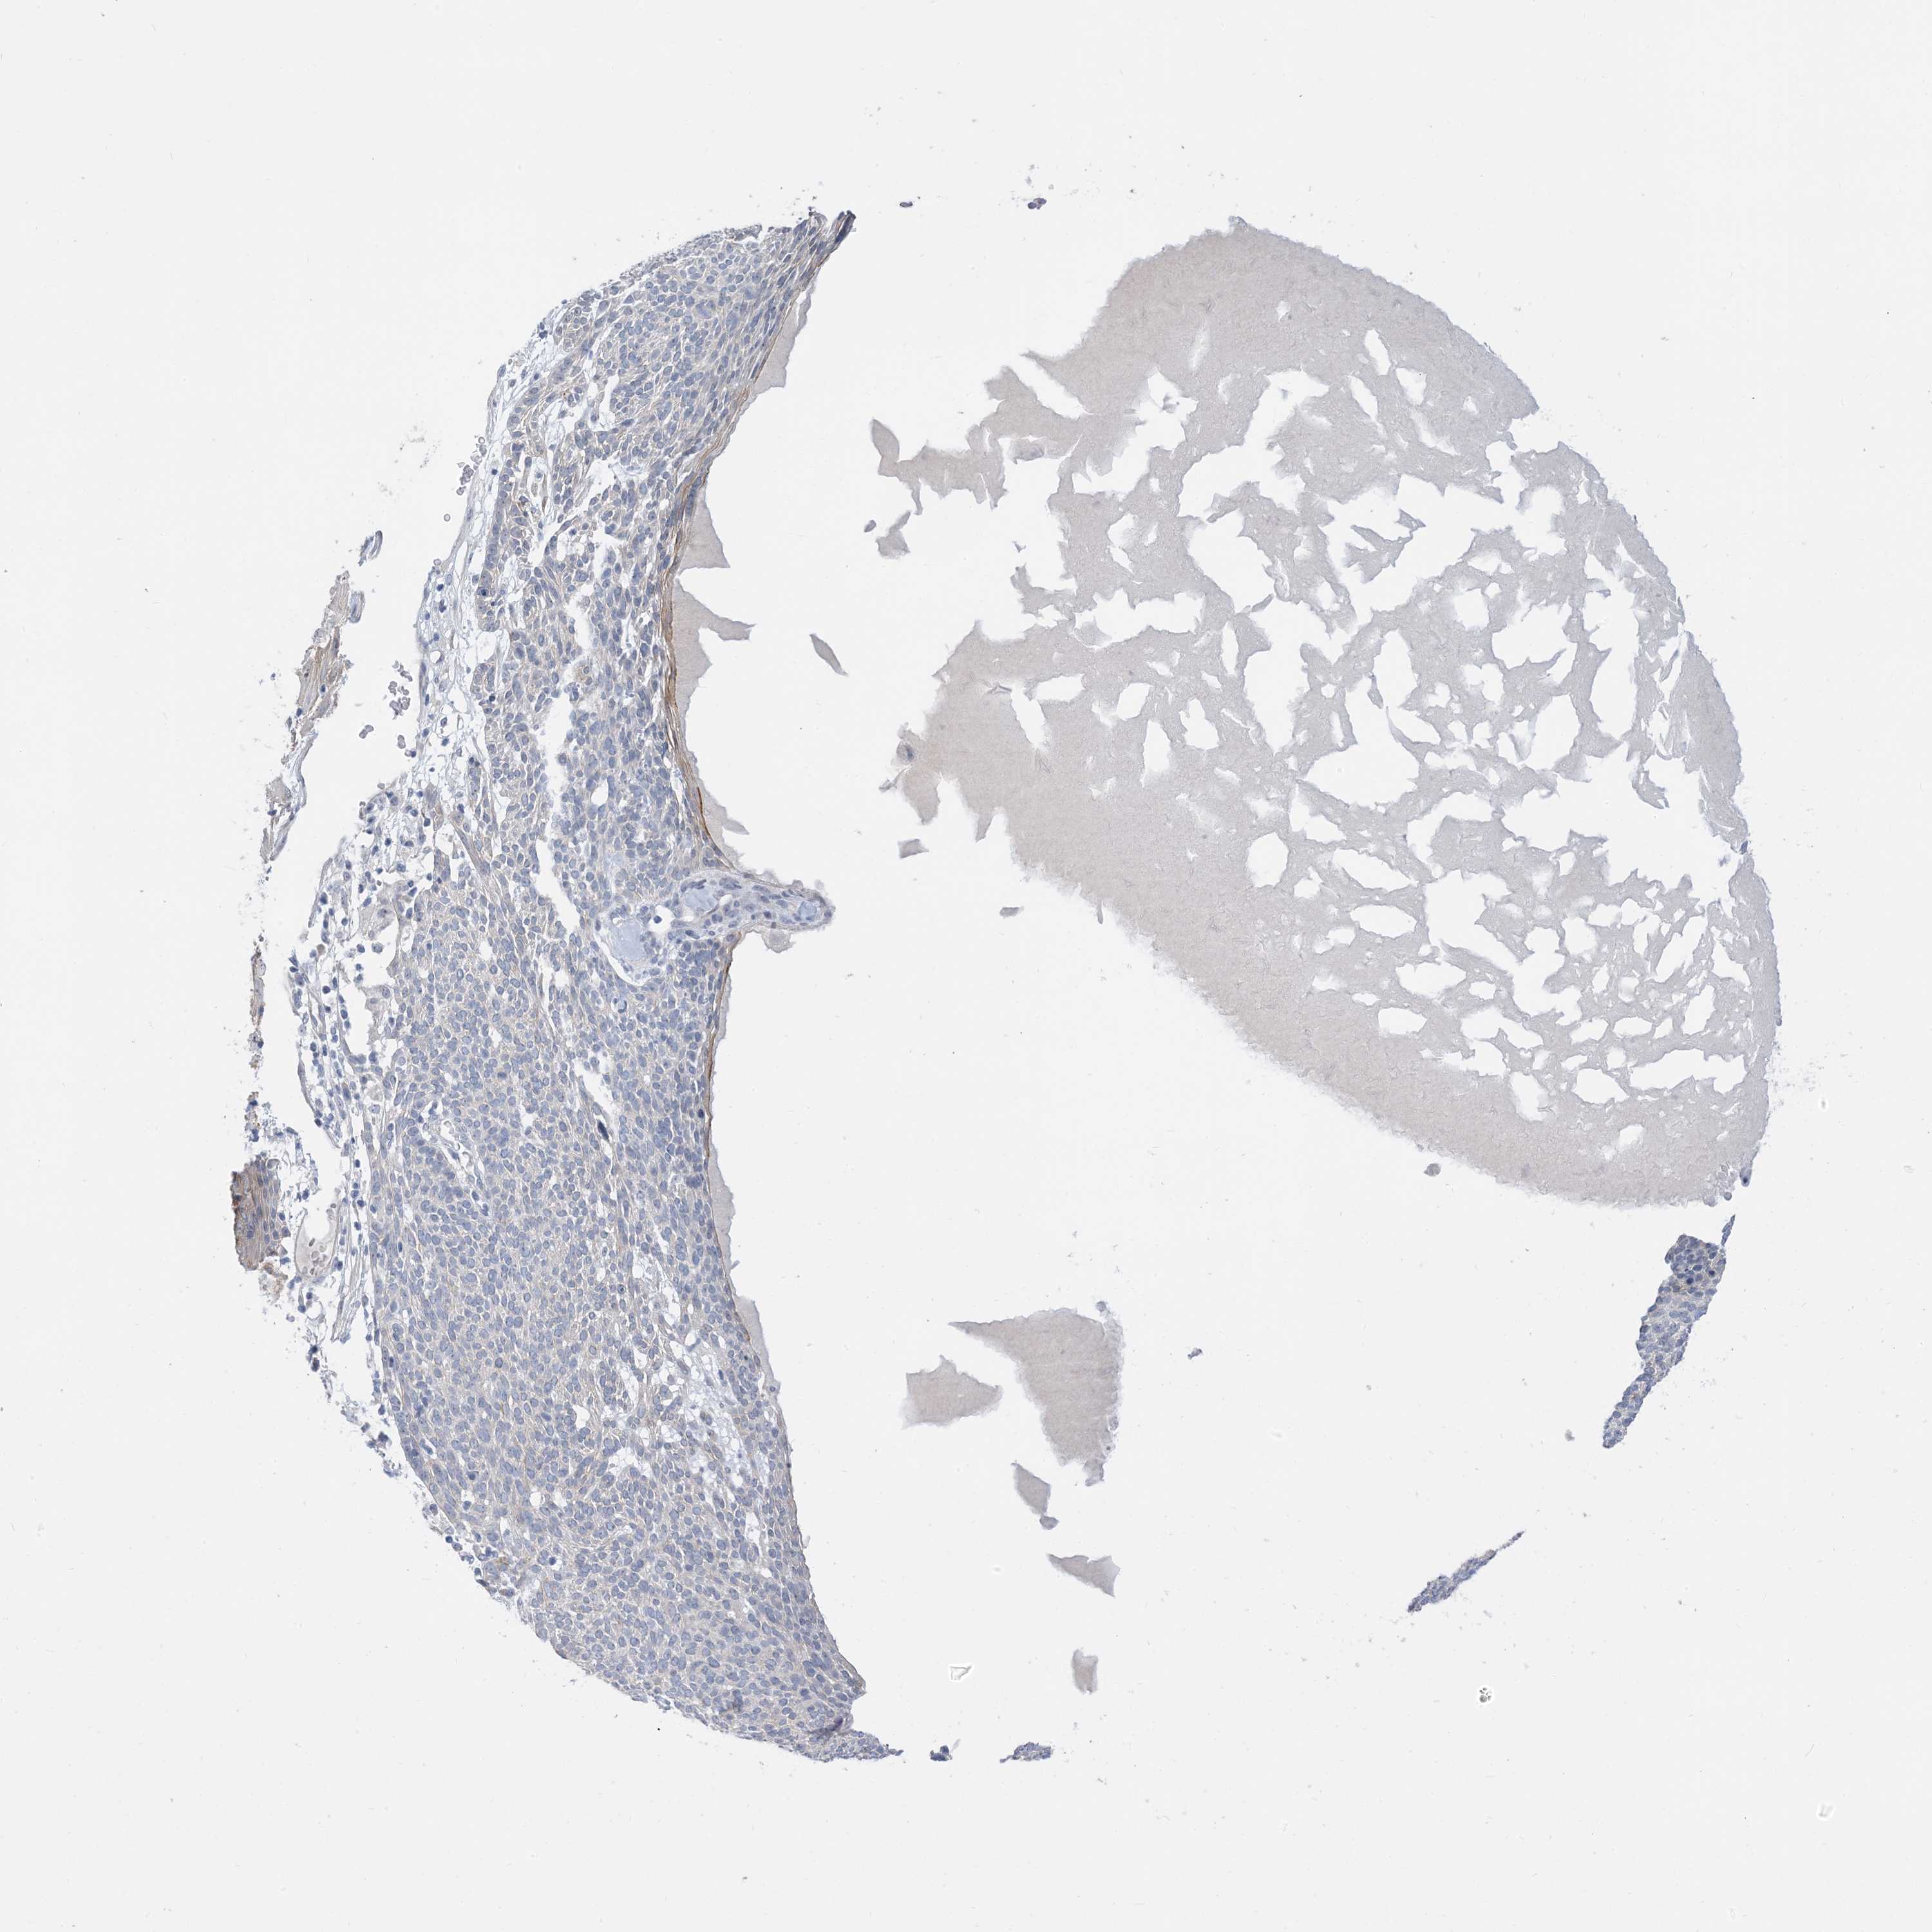

SKIN CANCER - Protein expressioni

A mouse-over function shows sample information and annotation data. Click on an image to view it in a full screen mode. Samples can be filtered based on level of antibody staining by selecting one or several of the following categories: high, medium, low and not detected. The assay and annotation is described here.

Each image is clickable and will lead to virtual microscopy that enables deeper exploration of all samples and also displays staining intensity scores, fraction scores and subcellular localization as well as patient and tissue information for each sample.

Antibody HPA035664

Squamous cell carcinoma, NOS

Squamous cell carcinoma, metastatic, NOS